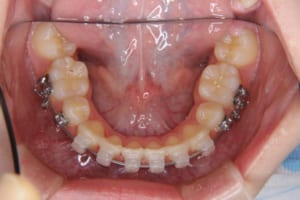

治療中